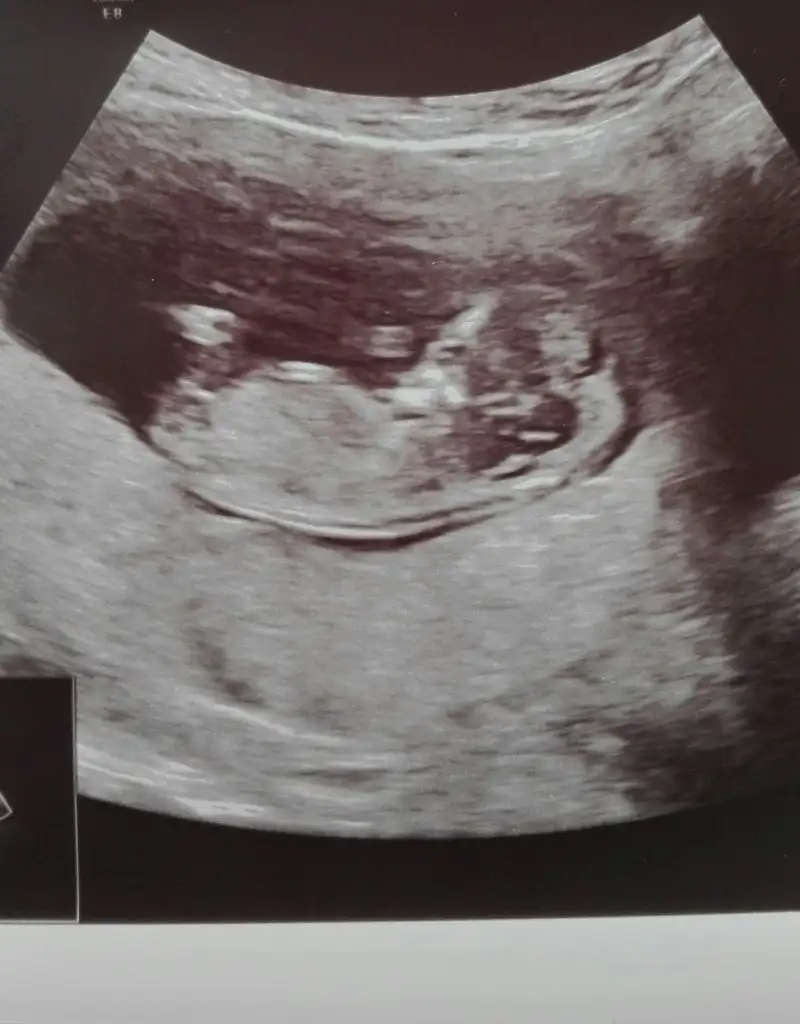

Kizlar sizce bebisimin cinsiyeti ne:KK48:

IMG_20191203_161946.webp